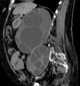

Pseudoenlargement of psoas muscle

Enlarged iliopsoas muscle